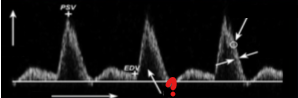

What represents the question mark on this image?

Velocity